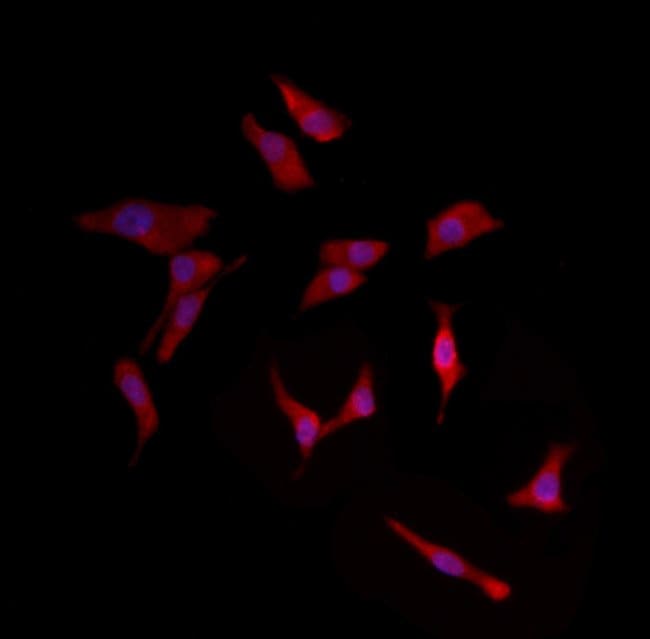

Herpes simplex virus 2 gD antibody The Native Antigen Company Does Antibodies Mean I Have Herpes These proteins are designed to neutralize the incoming bacteria, virus, or. Web the herpes simplex virus antibodies test is a blood test that screens for the herpes simplex virus (hsv). Culturing a sample from an. Web before your body can begin to fight an infection, it must produce proteins called antibodies. Web if herpes is strongly suspected but the blood. Does Antibodies Mean I Have Herpes.